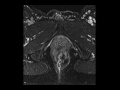

Rectal cancer with involvement of sphincters

MR images demonstrate an aggressive rectal cancer extending downwards to involve the levator ani as well as the internal and external sphincters.